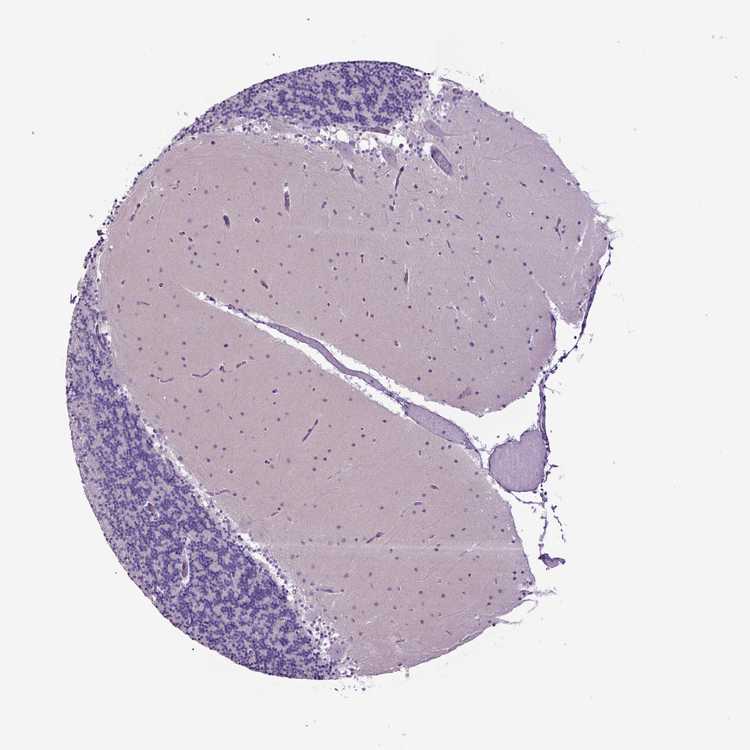

CEREBELLUM - Antibody stainingi

Antibody staining in the annotated cell types in the current human tissue is reported as not detected, low, medium, or high, based on conventional immunohistochemistry profiling in selected tissues. This score is based on the combination of the staining intensity and fraction of stained cells.

Each image is clickable and will lead to virtual microscopy that enables deeper exploration of all samples and also displays staining intensity scores, fraction scores and subcellular localization as well as patient and tissue information for each sample.

Antibody CAB033645

Purkinje cells Not detected

Cells in granular layer Not detected

Cells in molecular layer Not detected